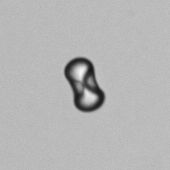

CaOx - Biconcaaf

Calciumoxalaatmonohydraat-kristallen komen voor in verschillende vormen, zoals ovaal, ovaal-rechthoekig, haltervormig (‘dumbbell’), biconcave schijfjes en langwerpige hexagonale structuren. Hun grootte kan sterk variëren: van zeer klein tot vrijwel beeldvullend. Ze zijn doorgaans kleurloos en vertonen sterke dubbele breking onder gepolariseerd licht.